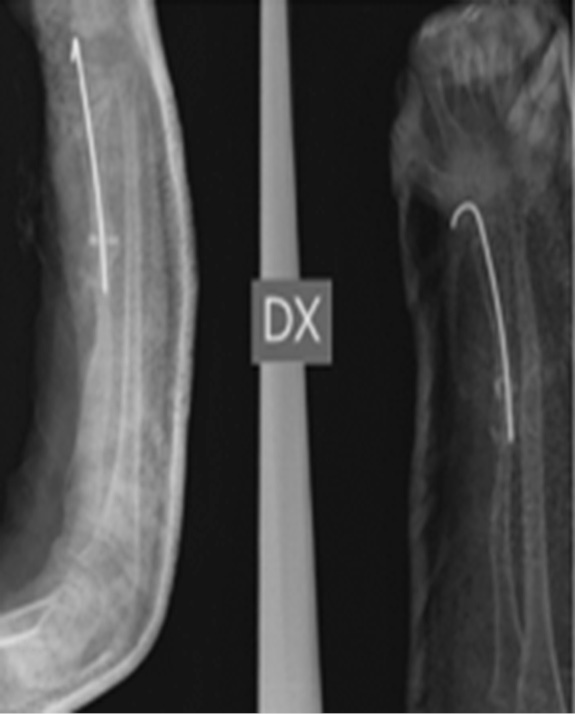

В июне 2015 г. были отмечены признаки местной резорбции кости в области переломов, и в связи с подозрением на синдром Горхема – Стоута проведены магнитно-резонансная томография и консультация со специалистом по редким заболеваниям (рис. 3).

Рис. 3. В области переломов — признаки локальной резорбции кости